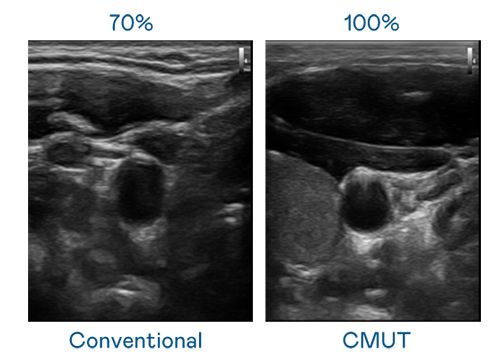

CMUT 技術是一種用電容式微機電元件來產生超音波訊號的技術。與傳統 PZT 壓電式技術相比,CMUT 頻寬增加 30%,更寬頻的超音波訊號讓影像解析度大幅提升,是實現高影像品質醫療超音波掃描、促進精準醫療發展的關鍵技術。

超音波影像的解析度高低,首先取決於探頭能發出的訊號頻寬。w66利来 CMUT 可提供高清晰的超音波訊號,提供高頻寬、高靈敏度、影像紋理細節更高的超音波影像,協助醫護人員縮短影像判讀時間及利用精準的醫療影像進行診斷。